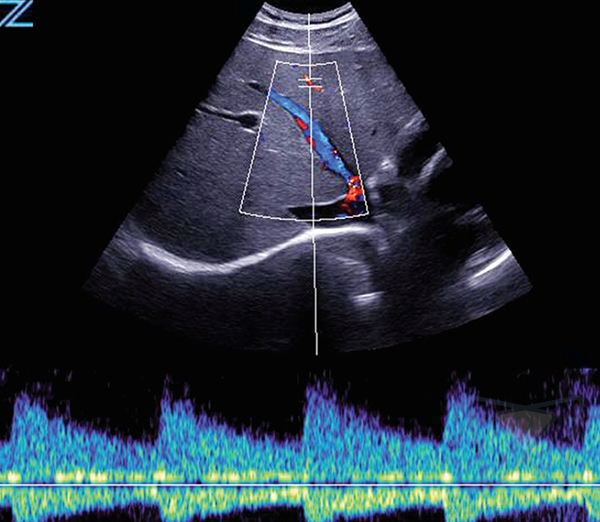

Система Zonare ZS3 оснащена инновационной программной технологией ZONE Sonography Technology (ZST), обеспечивающей диагностические преимущества в любых клинических ситуациях. Сфокусированное по всей глубине сканирования, четкое и детализированное изображение в В-режиме в сочетании с визуализацией в доплеровском режиме, позволяют охватить весь спектр клинических потребностей. УЗИ аппарат премиум класса подходит для проведения качественных исследований в любых условиях, благодаря быстрому переключению режимов и эргономичной, легкой портативной конструкции.

- Триплексный режим, с возможностью сохранения и просмотра кинопетли,

- Постоянно-волновой доплер с поддержкой на различных типах датчиках,